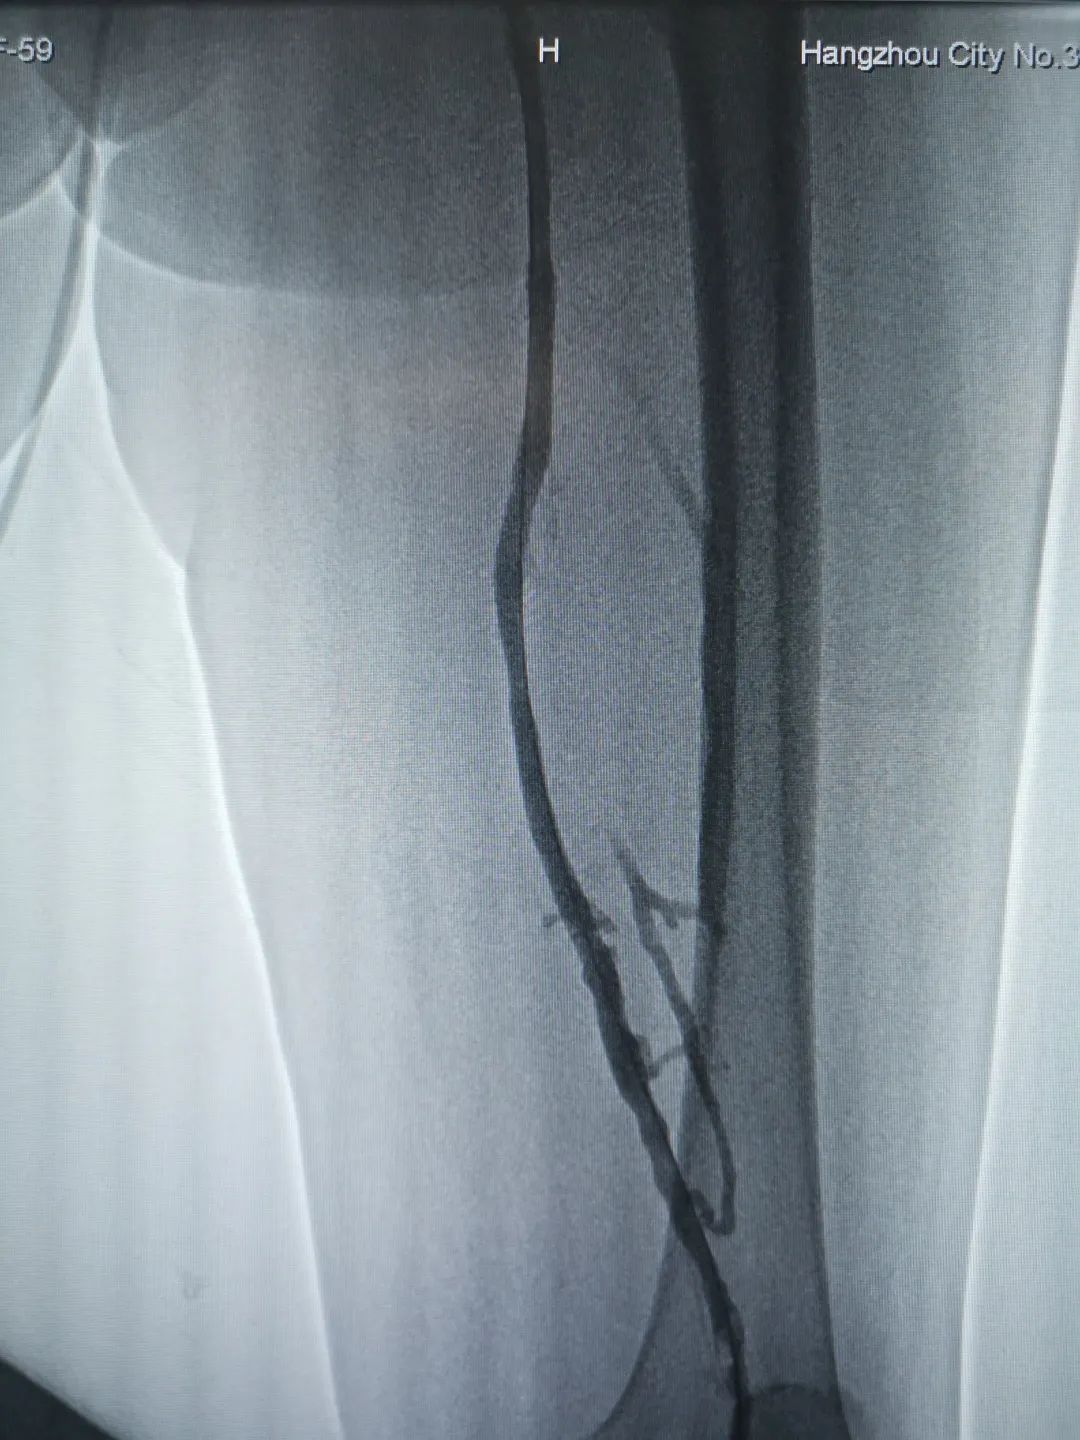

經(jīng)過超聲檢查,郭阿姨被確診為深靜脈血栓。

“原本以為是單純深靜脈血栓,但是術(shù)前檢查發(fā)現(xiàn)她還有左髂靜脈受壓狹窄,除了要行下肢靜脈吸栓、溶栓手術(shù),還需要在術(shù)中放入血管支架!最終,郭阿姨接受了微創(chuàng)吸栓治療,同時(shí),還在術(shù)中置入了讓血管恢復(fù)正常管徑的支架,“一站式”解決了血管問題。血栓會(huì)導(dǎo)致肢體腫脹,局部張力升高,使皮膚出現(xiàn)張力性水皰、硬塊、失去彈性等情況。若繼續(xù)進(jìn)展,則會(huì)發(fā)生皮膚缺血、蒼白、壞死、潰瘍、出血,最終可能導(dǎo)致截肢。有的血栓一旦脫落,會(huì)隨血管活動(dòng),進(jìn)入肺動(dòng)脈,發(fā)生肺栓塞,威脅生命。